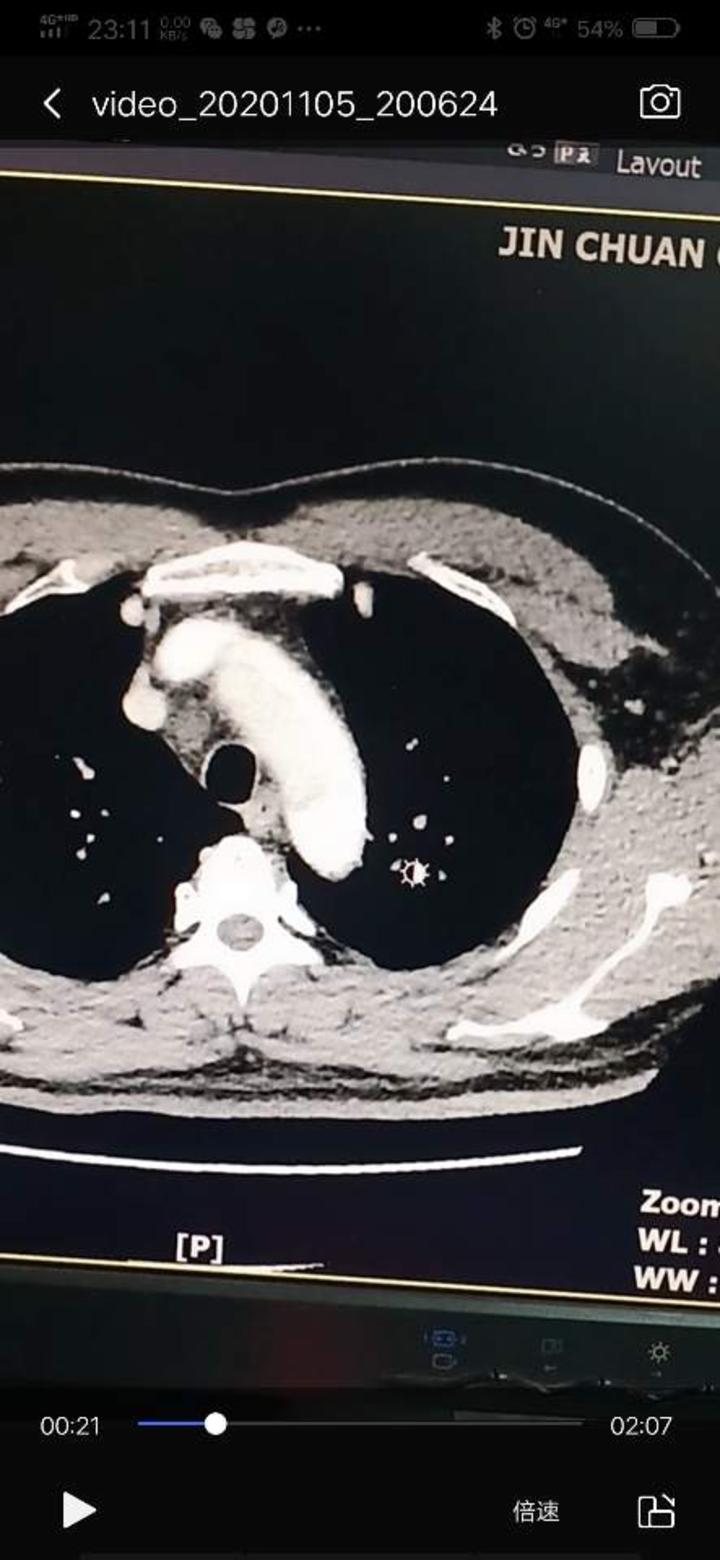

胸ct平扫示:①升主动脉明显增粗;②心影增大;不除外心包少量积液,请

胸部增强ct显示:升主动脉与降主动脉旁见新月形未强化低密度影.

升主动脉内可见套筒样改变,非常典型的主动脉夹层.